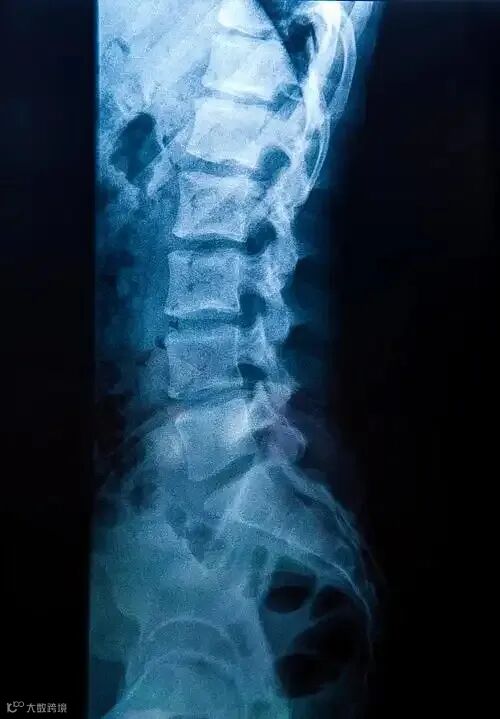

在医疗领域,医疗影像如同医生洞察人体内部奥秘的“眼睛”,是疾病诊断的关键依据。然而,传统的医疗影像解读往往依赖医生的经验和专业知识,过程复杂且耗时。随着人工智能(AI)技术的飞速发展,它在医疗影像处理中的应用为诊断报告可视化带来了全新的可能,极大地改变了医疗诊断的模式。

以往,医生面对X光、CT、MRI等各种医疗影像时,需要逐帧仔细观察,从中寻找病变的蛛丝马迹。这不仅考验医生的专业技能,而且长时间的阅片工作容易导致视觉疲劳,影响诊断的准确性。例如在肺癌的早期诊断中,肺部的微小结节在CT影像上可能并不明显,经验不足的医生可能会错过关键信息,从而延误病情。

AI的介入为这一困境带来了转机。AI算法具有强大的数据处理和分析能力,能够快速对大量的医疗影像数据进行学习和分析。通过深度学习技术,AI可以识别影像中的各种特征,准确地定位病变区域,并对病变的性质进行初步判断。以乳腺癌的诊断为例,AI系统可以对乳腺钼靶影像进行全面扫描,识别出可疑的肿块或钙化点,并通过算法计算出病变的概率。这一过程大大缩短了诊断时间,提高了诊断的效率。

更为重要的是,AI能够将复杂的影像信息转化为直观易懂的可视化报告。传统的诊断报告通常以文字形式呈现,对于患者来说,理解起来具有一定的难度。而AI生成的可视化报告则不同,它可以通过图形、图表等形式,将病变的位置、大小、形态以及相关的诊断数据直观地展示出来。比如,利用三维重建技术,AI可以将肝脏的CT影像重建为立体模型,清晰地显示出肿瘤的具体位置和与周围组织的关系。医生可以通过旋转、缩放等操作,从不同角度观察病变情况,为制定治疗方案提供更准确的依据。患者也能够更直观地了解自己的病情,增强对治疗的信心。